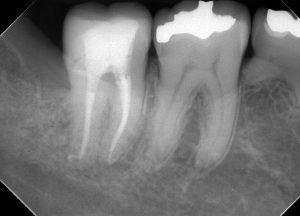

レントゲンを見てみよう。

(術前のレントゲン、CT)

半埋伏智歯(半分歯茎の中に埋まっている親知らず)の影響で、右下7番の遠心にう蝕があったであろうことが分かる。

この場所は、親知らずが無ければ、本来虫歯ができるはずがない場所だ。

このようなことがあるので、半埋伏智歯は早めに抜いておいた方が良いのかもしれない。

一つ言えることは、この場所に虫歯ができると「治療が非常に難しくなる」ということである。

理由は簡単、見えにくいからだ。

現に過去の虫歯治療の状態は、問題だらけだ。

・虫歯も取りきれていない

・裏層したセメントは大きくはみ出している

・修復物の適合も全くあっていない

見えない場所を、盲目的に、感覚頼りに治療したのだろう。

そして、結果的に神経が死んでしまい、かなり広範囲に骨が溶けてしまっている。